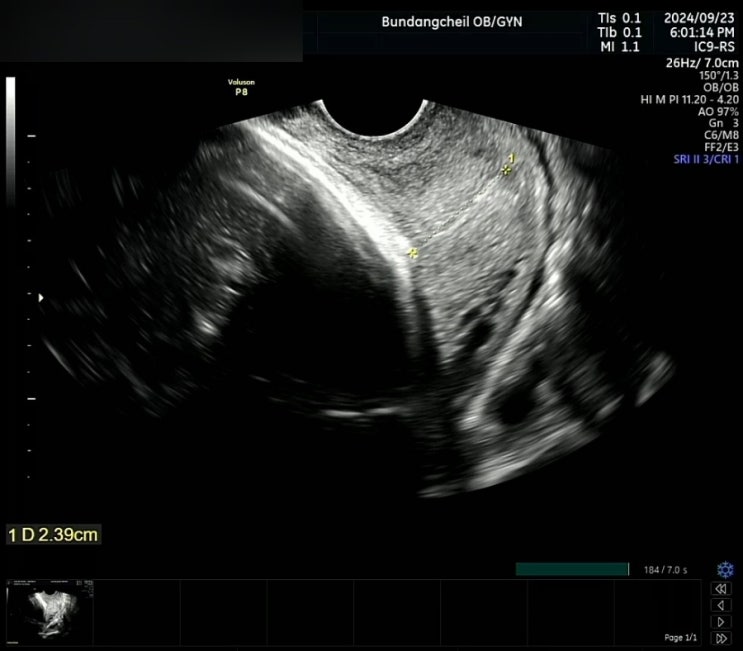

[둘째 임신] 33주차 / 자궁경부 길이 짧음 / 조기 자궁수축 / 분당제일여성병원 입원 (4)

[둘째 임신] 33주차 / 자궁경부 길이 짧음 / 조기 자궁수축 / 분당제일여성병원 입원 (3)

[둘째 임신] 32주차 5일 / 자궁경부길이 짧음 / 조기자궁수축 / 분당제일여성병원 입원 (2)

[둘째 임신] 32주차 4일 입원 / 자궁경부 짧음, 조금의 자궁수축